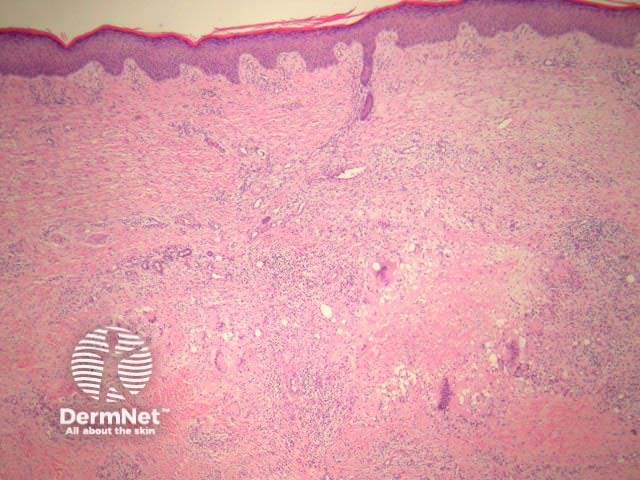

Palisading xanthogranulomas with foci of necrobiosis are found in the mid dermis and panniculus (Figures 1, 2). Involvement of the panniculus is septal (figure 2) and may mimic panniculitis. Focal areas of necrobiotic collagen appear as amorphous eosinophilic debris (Figure 3) and often contain cholesterol clefts. Granulomas consist of foamy histiocytes (Figure 4, arrow), and giant cells (Figure 5). Both touton and foreign body giant cells are found. Quite striking angulated giant cells with darkly staining nuclei adjacent to areas of necrobiosis are a characteristic feature. Plasma cells are typically prominent. Sometimes there are dense lymphoid infiltrates with germinal centres.

Figure 1